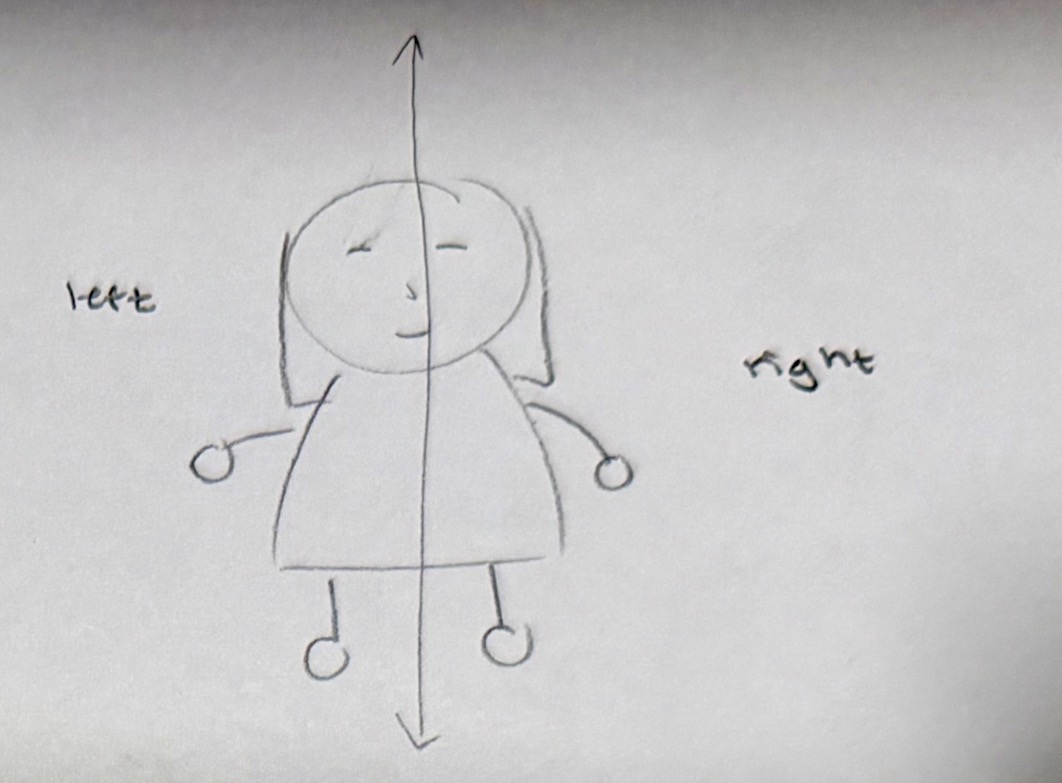

Sagittal section

vertical section splitting the body into a right and left side

Medial

towards the middle

Lateral

away from center of body (towards the sides)